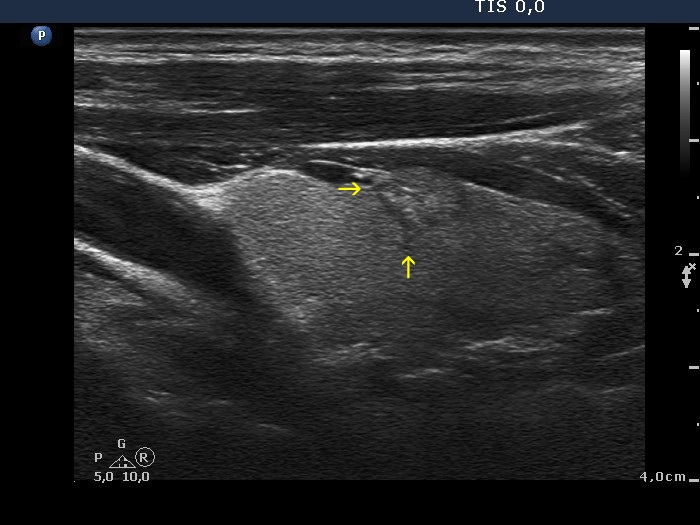

Papillary carcinoma (histology) - case conp006

Longitudinal scan

The tumor spreads into the normal parenchyma with elongated projections which have sharp edges (yellow arrows).